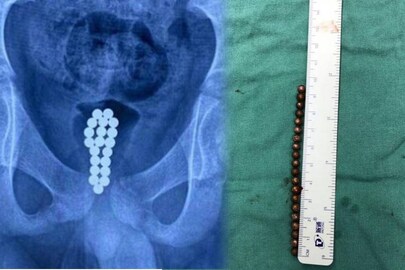

പതിനൊന്നുകാരൻ തന്റെ ലിംഗത്തിനുള്ളിലേക്ക് തള്ളിക്കയറ്റിയത് 20 കാന്തിക ബോളുകൾ. മാതാപിതാക്കളോടുപോലും പറയാതെ വേദന കടിച്ചമർത്തിയത് ഒരാഴ്ചക്കാലം. ദക്ഷിണ ചൈനയിലെ ഡോങ്ഗുവാൻ സ്വദേശിയായ കുട്ടിയാണ് കൗതുകം സഹിക്കാനാകാതെ ഈ പണി ചെയ്തത്. ഒടുവിൽ മുത്രസഞ്ചിയിൽ തങ്ങിനിന്ന കാന്തിക ബോളുകൾ നീക്കം ചെയ്യാൻ ശസ്ത്രക്രിയ വേണ്ടിവന്നു.

രക്തം കലർന്ന മൂത്രമാണ് പുറത്തുവന്നത്. കടുത്ത വേദനയുമുണ്ടായിരുന്നു. എന്നിട്ടും ഒരാഴ്ചക്കാലം ഇക്കാര്യം രക്ഷിതാക്കളോട് പറയാതെ കുട്ടി മറച്ചുവെച്ചു. വേദന സഹിക്കാവുന്നതിലും അപ്പുറമായതോടെ പറഞ്ഞുവെങ്കിലും കാന്തിക ബോളുകൾ ഉള്ളിലേക്ക് കടത്തിയ കാര്യം കുട്ടി രക്ഷിതാക്കളോട് മറച്ചുവെച്ചു. അടുത്തുള്ള ആശുപത്രിയിലാണ് ചെക്ക് അപ്പിനായി കൊണ്ടുപോയത്. അവിടത്തെ ഡോക്ടറാണ് ഇക്കാര്യം കണ്ടുപിടിച്ചത്. ആശുപത്രിയിലെത്തിയപ്പോൾ കടുത്ത അണുബാധയും കുട്ടിയെ ബാധിച്ചിരുന്നു.

ഡോങ്ഗുവാനിലെ കുട്ടികളുടെ ആശുപത്രിയിലെ ചീഫ് യൂറോളജിസ്റ്റായ ഡോ. ലി ഹോങ്ഹുയി ആണ് എൻഡോസ്കോപ്പി നടത്തിയത്. ശസ്ത്രക്രിയ കൂടാതെ 20 കാന്തിക ഗോളങ്ങൾ പുറത്തെടുക്കുക അസാധ്യമായിരുന്നുവെന്നും അദ്ദേഹം പറഞ്ഞു. മൂത്രനാളിയിലൂടെ ഇവ പുറത്തെടുക്കുന്നത് പരിക്ക് ഗുരുതരമാകുമെന്ന ആശങ്കയും ഡോക്ടർ പങ്കുവെച്ചു. പിന്നീട് ശസ്ത്രക്രിയയിലൂടെ ബോളുകളെല്ലാം നീക്കം ചെയ്തു.